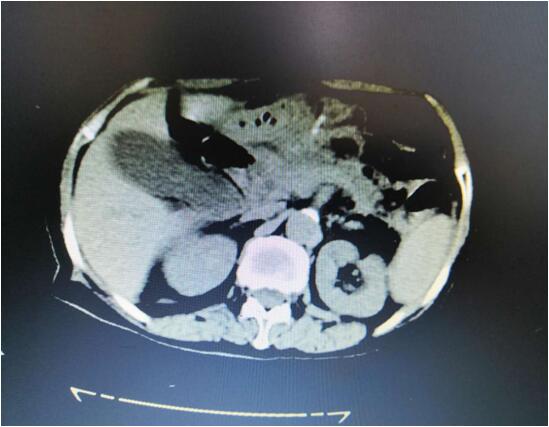

患者B,女,51歲,因牙齦出血1年入院,入院診斷為:乙肝,肝炎后肝硬化,門脈高壓癥,巨脾,脾亢,白細胞、血小板減少,中度貧血。5年前,曾在外院行介入脾栓塞術(shù),脾臟不僅沒有縮小,反而越來越大,脾下緣已經(jīng)超過腹部正中線、抵達臍部,就像幾個月“身孕”的婦女,給病人帶來巨大身心負擔(dān)。

(術(shù)前腹部CT顯示巨脾)